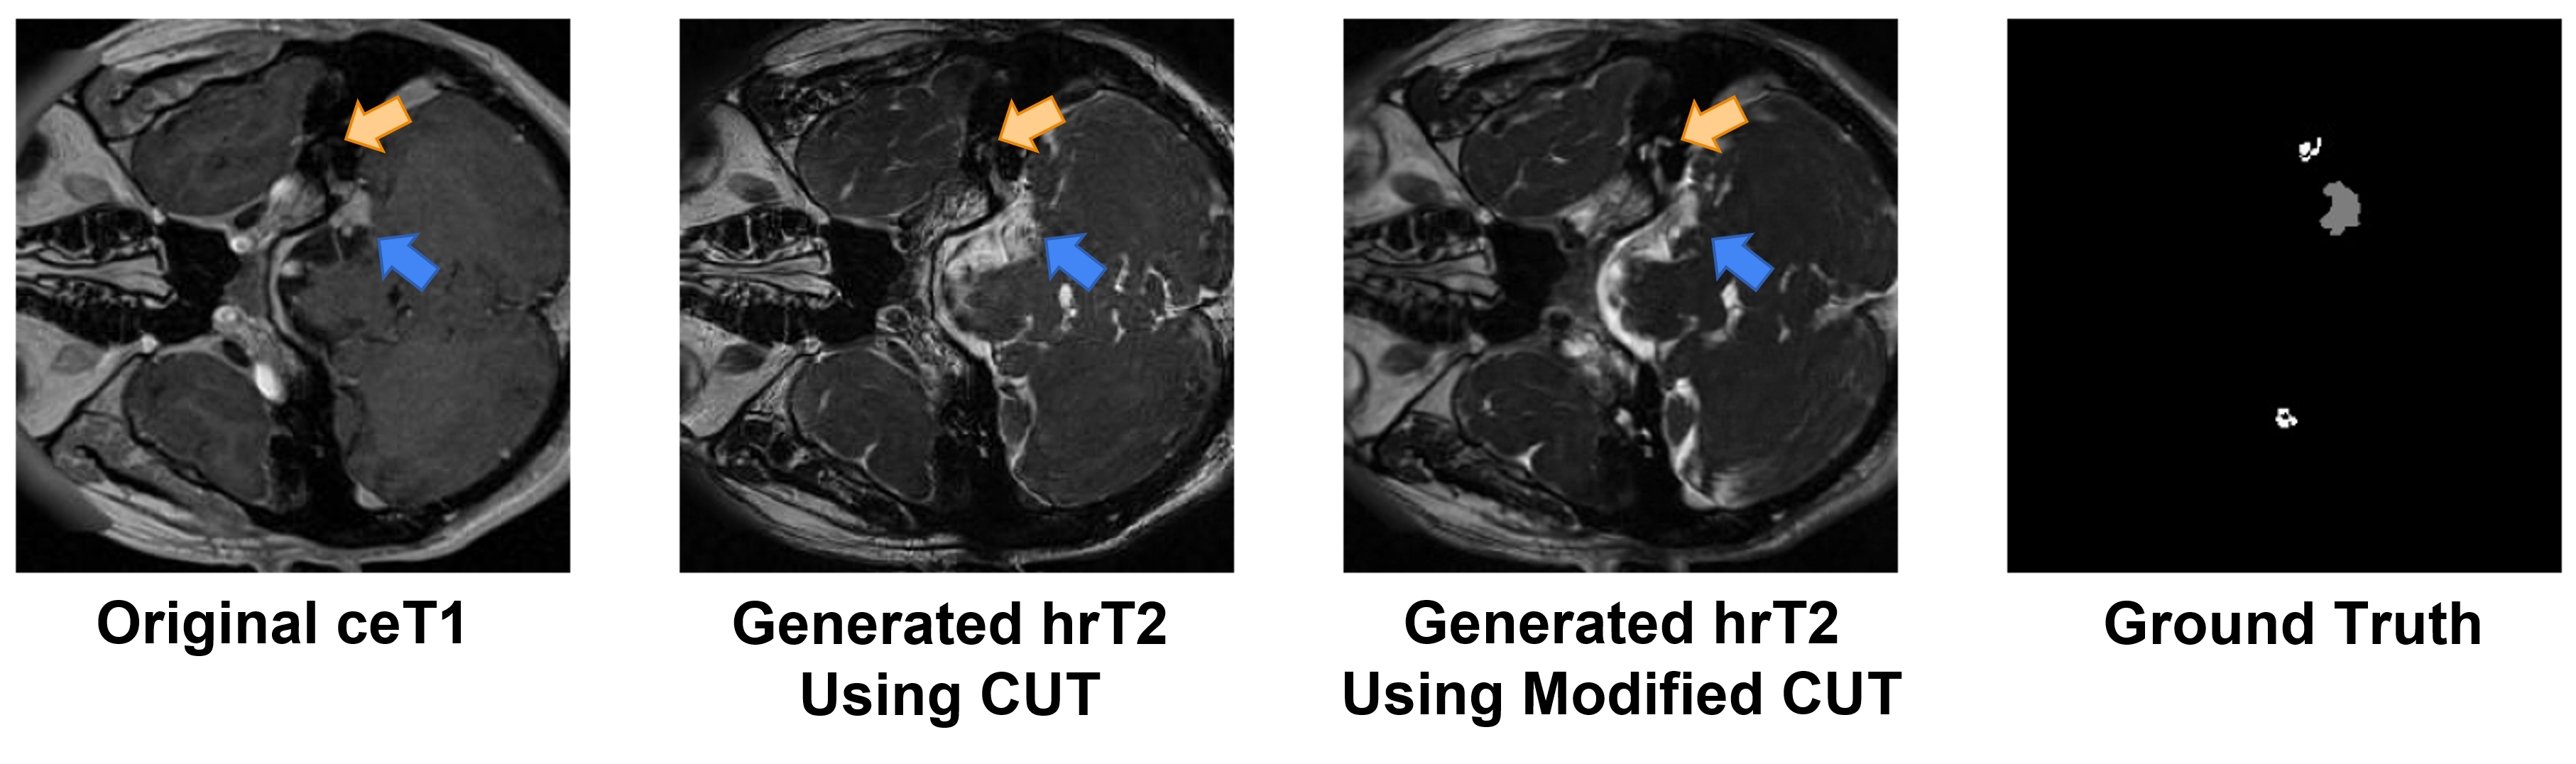

To close the domain gap across the modalities, we first conduct image-level domain adaptation to generate synthetic target samples. In this regard, the model trained on the synthetic target images will be used for VS and Cochlea segmentation on real hrT2 scans. For unpaired image-to-image translation, we adopt the Contrastive Unpaired Translation (CUT) [21] as our backbone since it is faster and less memory-intensive than CycleGAN [36]. Moreover, we enhance the 2D CUT with an additional segmentation decoder for maintaining the structural information of VS and Cochlea (see Fig. 1). Specifically, a ResNet-based generator is used to translate images from the source domain to the target domain, while a PatchGAN discriminator is employed to distinguish between the real and generated images [21]. We follow the SIFA architecture [2] and connect two layers of the encoder, specifically at the last layer and the layer before the last downsampling, with the segmenter decoder to generate multi-level segmentation predictions. The segmentation loss can help the encoder focus more on areas related to the segmentation task and preserve the structure of VS and Cochlea in the translated images. In Fig. 2, we can observe that the modified CUT can better preserve the shape of the VS and Cochlea in comparison with the original CUT framework.